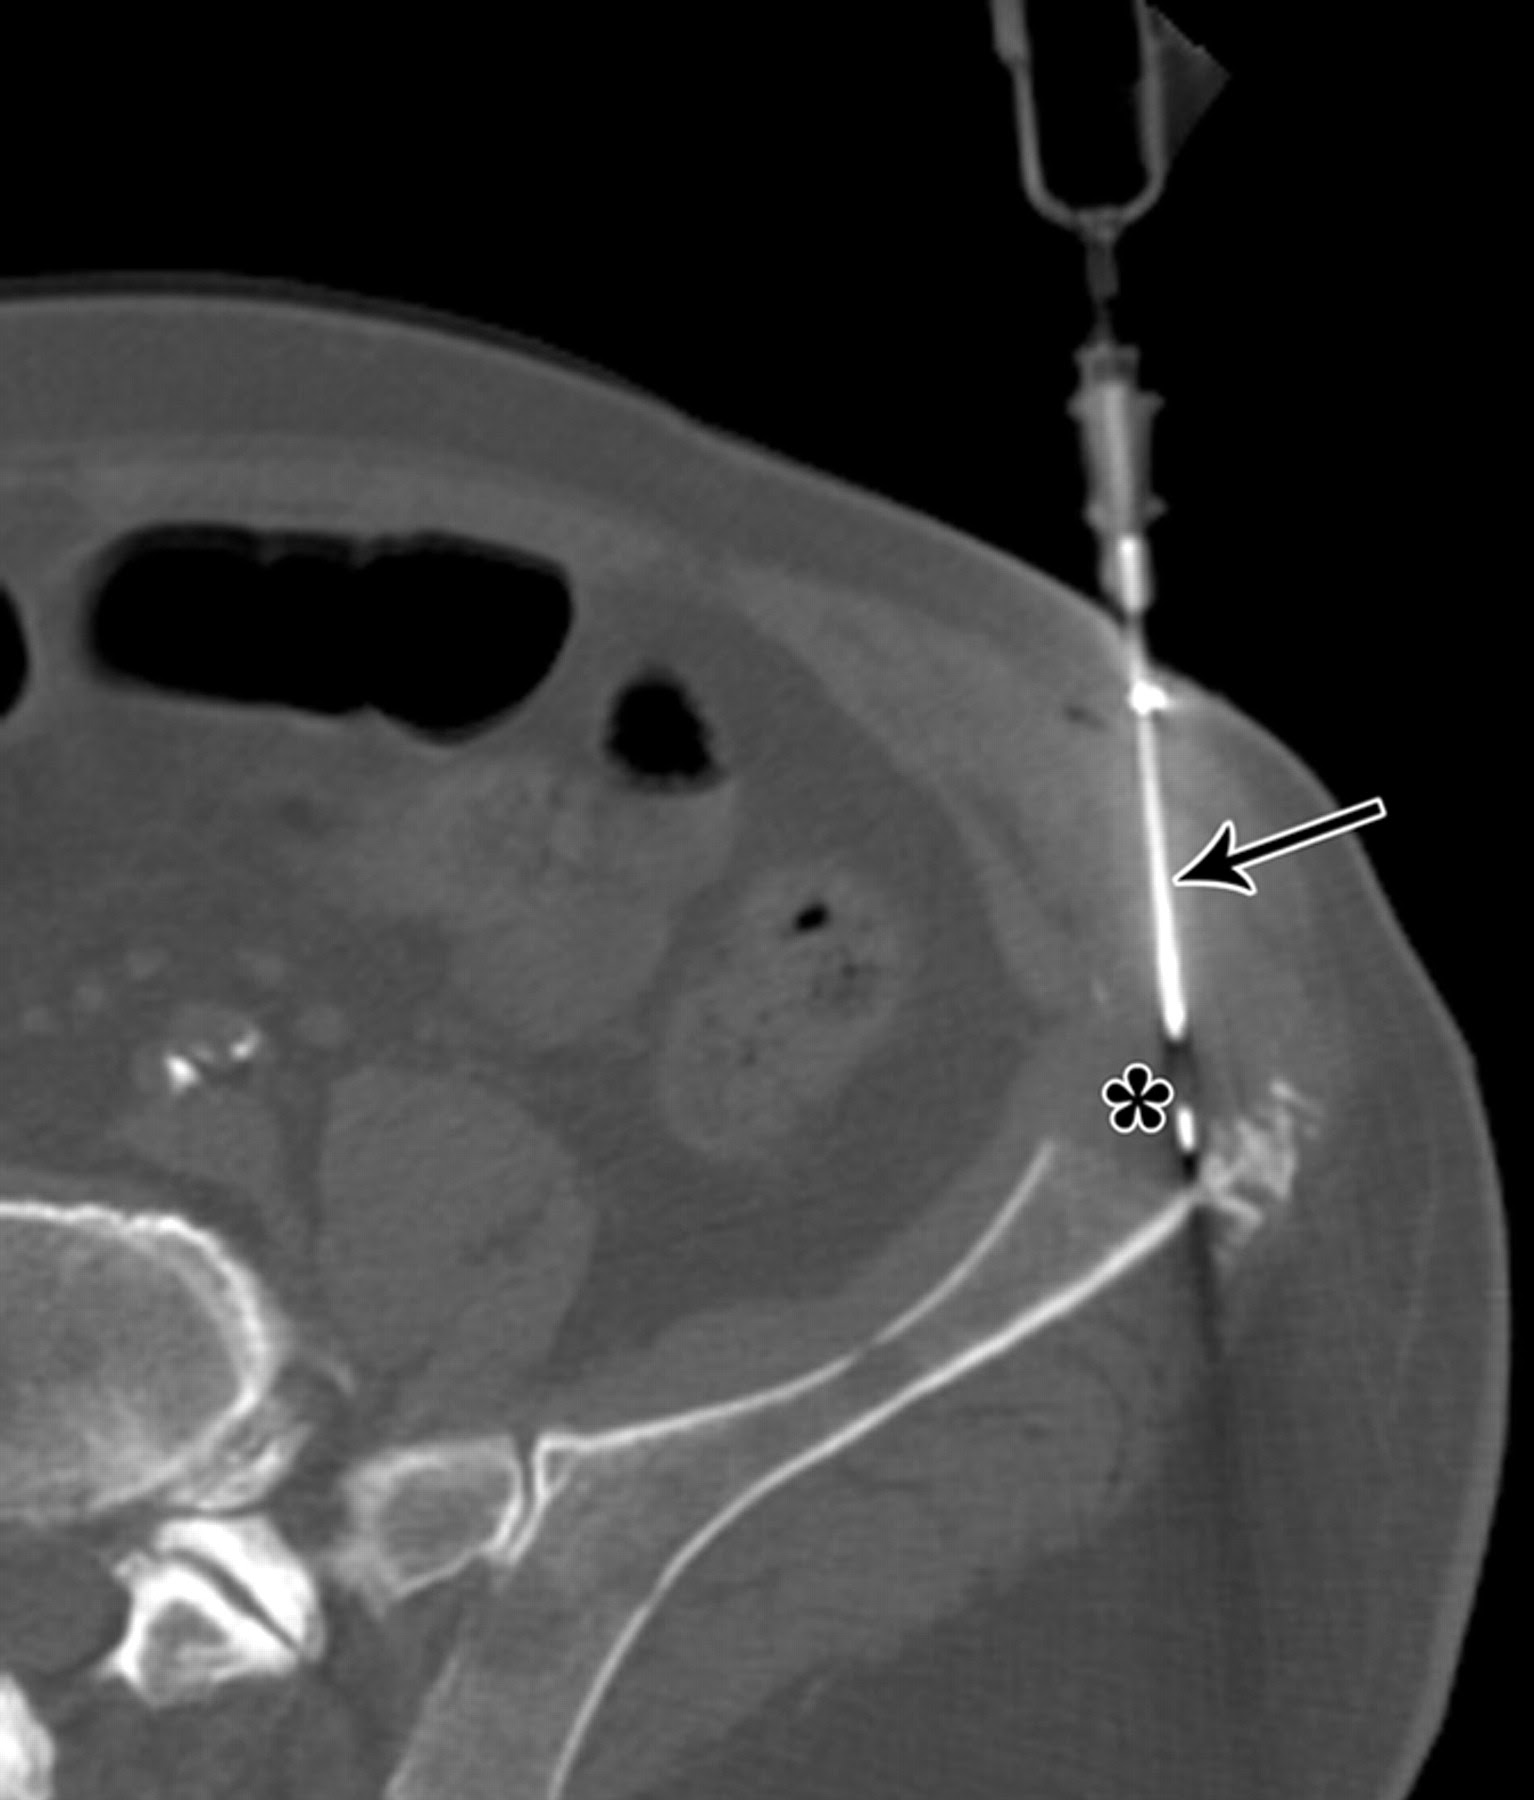

Biopsia ossea TC guidata

Una valutazione diagnostica per immagini accurata prima della biopsia è fondamentale, poiché può rendersi necessario eseguire ulteriori accertamenti.